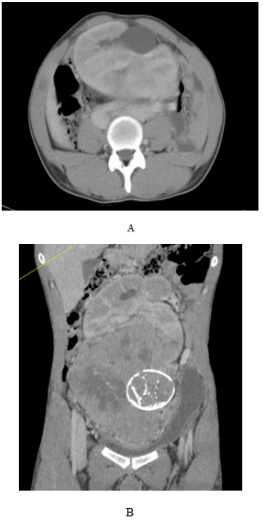

On physical examination, a nontender, firm mass was easily palpable in the left lower quadrant extending to the pelvic brim. Computed tomography Scan of the chest, abdomen, and pelvis revealed a pancake kidney with a large mass in the left moiety, measuring 150X110X200 mm. The tumor extended into the isthmus and appeared to abut or extend into the inferior right moiety, at the site of fusion of both moieties, just below the aortic bifurcation, with a macrocalcification (Figure 1). Bilateral renal arteries were arising from the ipsilateral external iliac arteries (Figure 2) with an accessory renal artery on the right side from the aorta. no metastasis was found.

Figure 1 Contrast-enhanced tomographic scan showing pancake kidney with a tumor at the lower pole with macrocalcification.